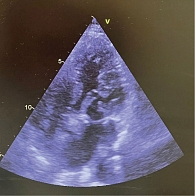

Рис. 5. Контрольная ЭхоКГ спустя год после кардиохирургического лечения. Опорное кольцо митрального клапана

Послеоперационный период протекал без осложнений. Пациентка выписана на восьмые сутки после операции с рекомендациями по дальнейшей реабилитации и приему лекарственной терапии (спиронолактон – 25 мг/сут; лозартан – 12,5 мг/сут; дапаглифлозин – 10 мг/сут; аторвастатин – 10 мг/сут; варфарин – 1,25 мг/сут). Через год по данным ЭхоКГ, гемодинамические параметры митрального клапана – в пределах нормы, локальная сократимость и глобальная функция ЛЖ сохранены, данных о перикардиальном и плевральном выпотах нет (рис. 5).